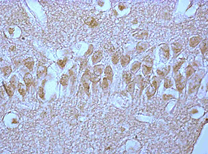

Figure 1: Bcl-2 content (in optical density units) in the cytoplasm of pyramidal neurons in the CA1 field of the rat hippocampus in partial (PCI), staged subtotal (SSCI), subtotal (SCI), and total (TCI) cerebral ischemia. Digital micrograph. Magnification x40.

Note: PCI – partial cerebral ischemia; SSCI – staged subtotal cerebral ischemia; SCI – subtotal cerebral ischemia.

In rats with PCI, no changes in Bcl-2 content relative to the level in the control group (p > 0.05) were detected (Table 1, Figure 1), indicating the preservation of normal apoptosis regulation in this type of CI.

In SCI, compared to the control group, the Bcl-2 content in the hippocampus decreased by 27% (p < 0>

Compared to PCI, the Bcl-2 content in SCI was lower by 30% (p < 0>

Compared to the control group, in the 1st subgroup of SSCI with a 7-day interval between CCA ligations, the Bcl-2 content did not change (p > 0.05), while in the 2nd and 3rd subgroups of SSCI (with intervals between ligations of 3 days and 1 day, respectively), it decreased by 27% (p < 0>

There were no differences in the Bcl-2 content in the cytoplasm of hippocampal neurons between the 1st subgroup of SSCI and the PCI group (p > 0.05), whereas compared to the SCI group, it was higher by 33% (p < 0>

Thus, the changes in Bcl-2 content in the 1st, 2nd, and 3rd subgroups of SSCI were multidirectional: in the 1st subgroup with the maximum interval between CCA ligations (7 days), it did not change, indicating normal regulation of apoptosis processes, while in the 2nd and 3rd subgroups, the Bcl-2 content decreased, which may indicate a lack of blockade of neuronal death processes in more severe forms of cerebral ischemia.